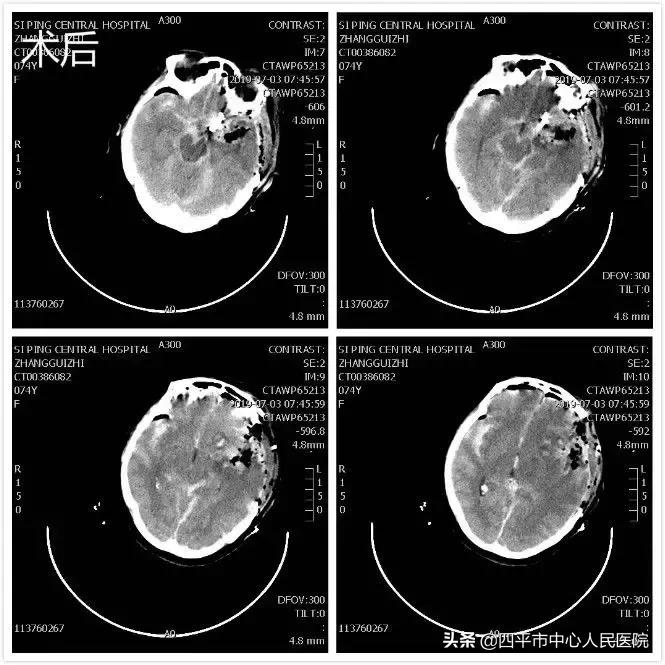

Case4 大量蛛网膜下腔出血颅内动脉瘤开颅探查术

患者张XX,于入院前2小时突发神志不清,伴恶心呕吐,呕吐物为胃内容物,四肢不动,伴尿*禁失**,无抽搐。由家属送至梨树县医院,行头CT检查提示脑出血,为求进一步治疗转送至我院,我院神经内科给予复查头CT提示大量蛛网膜下腔出血,首先颅内动脉瘤破裂所致,由于患者到我院时深度昏迷状态,呼吸微弱,HUNT-HESS分级5级,不适合行头部CTA检查及介入栓塞治疗,家属强烈要求手术治疗,请麻醉科行气管插管后入手术室,李晓东主任带领马龙急诊全麻下经左侧扩大翼点入路行右侧脑室外引流术及颅内动脉瘤探查术,术中探查患者左侧后交通动脉巨大瘤,临时阻断颈内动脉后给予确切夹闭,术中动脉瘤没再次有破裂出血。术后第1天,患者呈浅昏迷状态,刺痛可定位,四肢可自主活动。复查头部CT满意,查头部CTA见左侧后交通动脉瘤夹闭确切。但患者于术后第3天,出现迟发性脑内血肿,考虑到预后不好,家属放弃治疗出院,临出院时对我科李晓东主任及马龙医生的积极救治表示感谢。